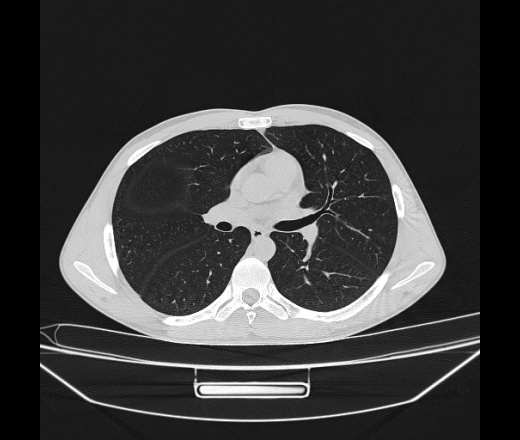

Молодой парень 18 лет, призывник, при прохождении ФЛС на верхушек левого легкого выявили очаги средней интснисвности с нечеткими контурами, тяжи. Сделали бок и томограммы 6-7-8. Везде описывают как очаговый твс. Вижу только перибронхиальный фиброз. Что за изменения в бронхах, указано нижи стрелками, тоже перибронхиальный?

Не стал бы говорить об очагах. Акцентировал бы не на фиброзе, а на тракционных бронхоэктазах. Не обязательно они результат tbc бронхов, но проверить не помешает.

Иван, пациент ведь уже "направлен с ОПТД", так?surprise Возвращайте его назад с заключением о возможном микобактериозе. Остаточные поствоспалительные ( посттуберкулёзные?) в дифряд.Очаговый твс с неясной активностью они уже себе "нарисовали", как я поняла.

+1 за микобактериоз.